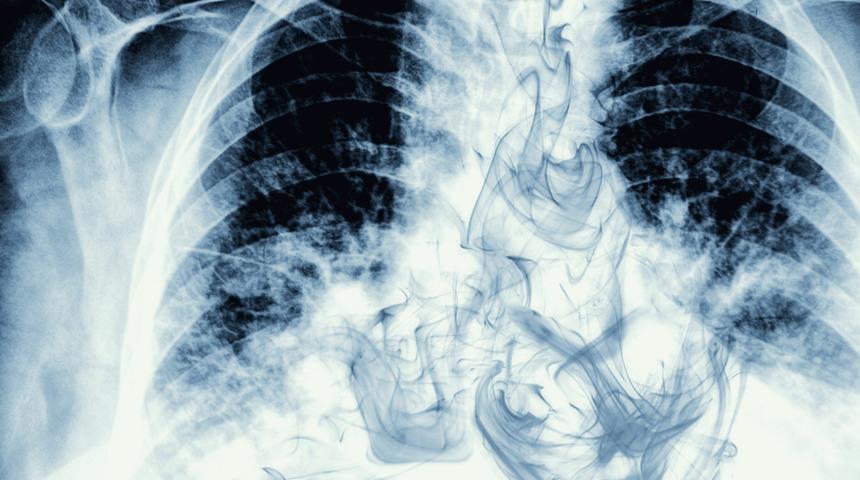

Asbestin neden olduğu hastalık: Akciğer zarı kanseri! Mezotelyoma nedir?

Dünyada ve ülkemizde görülen ve önümüzdeki son yirmi yılda artış beklenen Mezotelyoma, akciğer zarı kanseri olarak tabir edilir. Çok nadiren iyi huylu Mezotelyoma olsa da kötü huylu akciğer zarı kanseri olarak bilinen Malign Plevral Mezotelyoma (MPM) Asbest maruziyeti ile ortaya çıkan bir hastalıktır. En belirgin şikayeti nefes darlığı ve göğüs ağrısı olan Mezotelyoma omuz ağrısı, öksürük, kilo kaybı, ateş ve ses kısıklığı gibi belirtiler de veriyor.